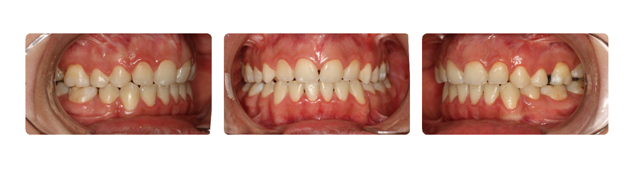

| دندانهای فک بالا و پایین دارای بی نظمی میباشند و با توجه به نبود فضا, بدون کشیدن دندان و توسط سیستم دیمون درمان میشوند: |

| درمان با براکتهای دیمون نتیجه بخش است: |

| پس از گذشت دو سال از درمان فک و دندانها مرتب شده و سر جای خود قرار گرفته اند: |

| همچنین پس از گذشت یک سال از پایان درمان همچنان نتیجه رضایت بخش است: |